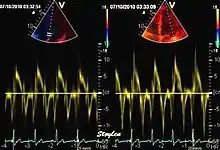

Like Doppler flow, tissue Doppler can be acquired both by spectral analysis (spectral density estimation) as pulsed Doppler[1] and by the autocorrelation technique as colour tissue Doppler[2] (duplex ultrasonography). While pulsed Doppler only acquires the velocity at one point at a time, colour Doppler can acquire simultaneous pixel velocity values across the whole imaging field. Pulsed Doppler on the other hand, is more robust against noise, as peak values are measured on top of the spectrum, and are unaffected of the presence of clutter (stationary reverberation noise).

Colour tissue Doppler

Unlike spectral Doppler, colour tissue Doppler samples velocities from all points of the sector, by shooting two pulses successively, and calculating the velocity from the phase shift between them by autocorrelation. The calculation is slightly different from the true Doppler effect, but the result becomes identical. This results in a single velocity value per sample volume. The result is a velocity field of (nearly) simultaneous velocity vectors towards the probe. The advantage of colour Doppler over spectral Doppler is that all velocities can be sampled simultaneously. The disadvantage is that if there is clutter noise (stationary reverberations), the stationary echoes will be integrated in the velocity calculation, resulting in an under estimate. As pulsed wave Doppler are displayed as a spectrum, the colour Doppler values will correspond to the mean of the spectrum (in the absence of clutter), giving slightly lower values. In the HUNT study, the difference in peak systolic values were about 1.5 cm/s.[26]

The local velocities are not the result of the local function, as segments are moved by the action of neighbouring segments. Thus the velocity differences velocity gradient are the main measure of regional contraction, and has become the most important employment of colour tissue Doppler, in the method of strain rate imaging.[27]